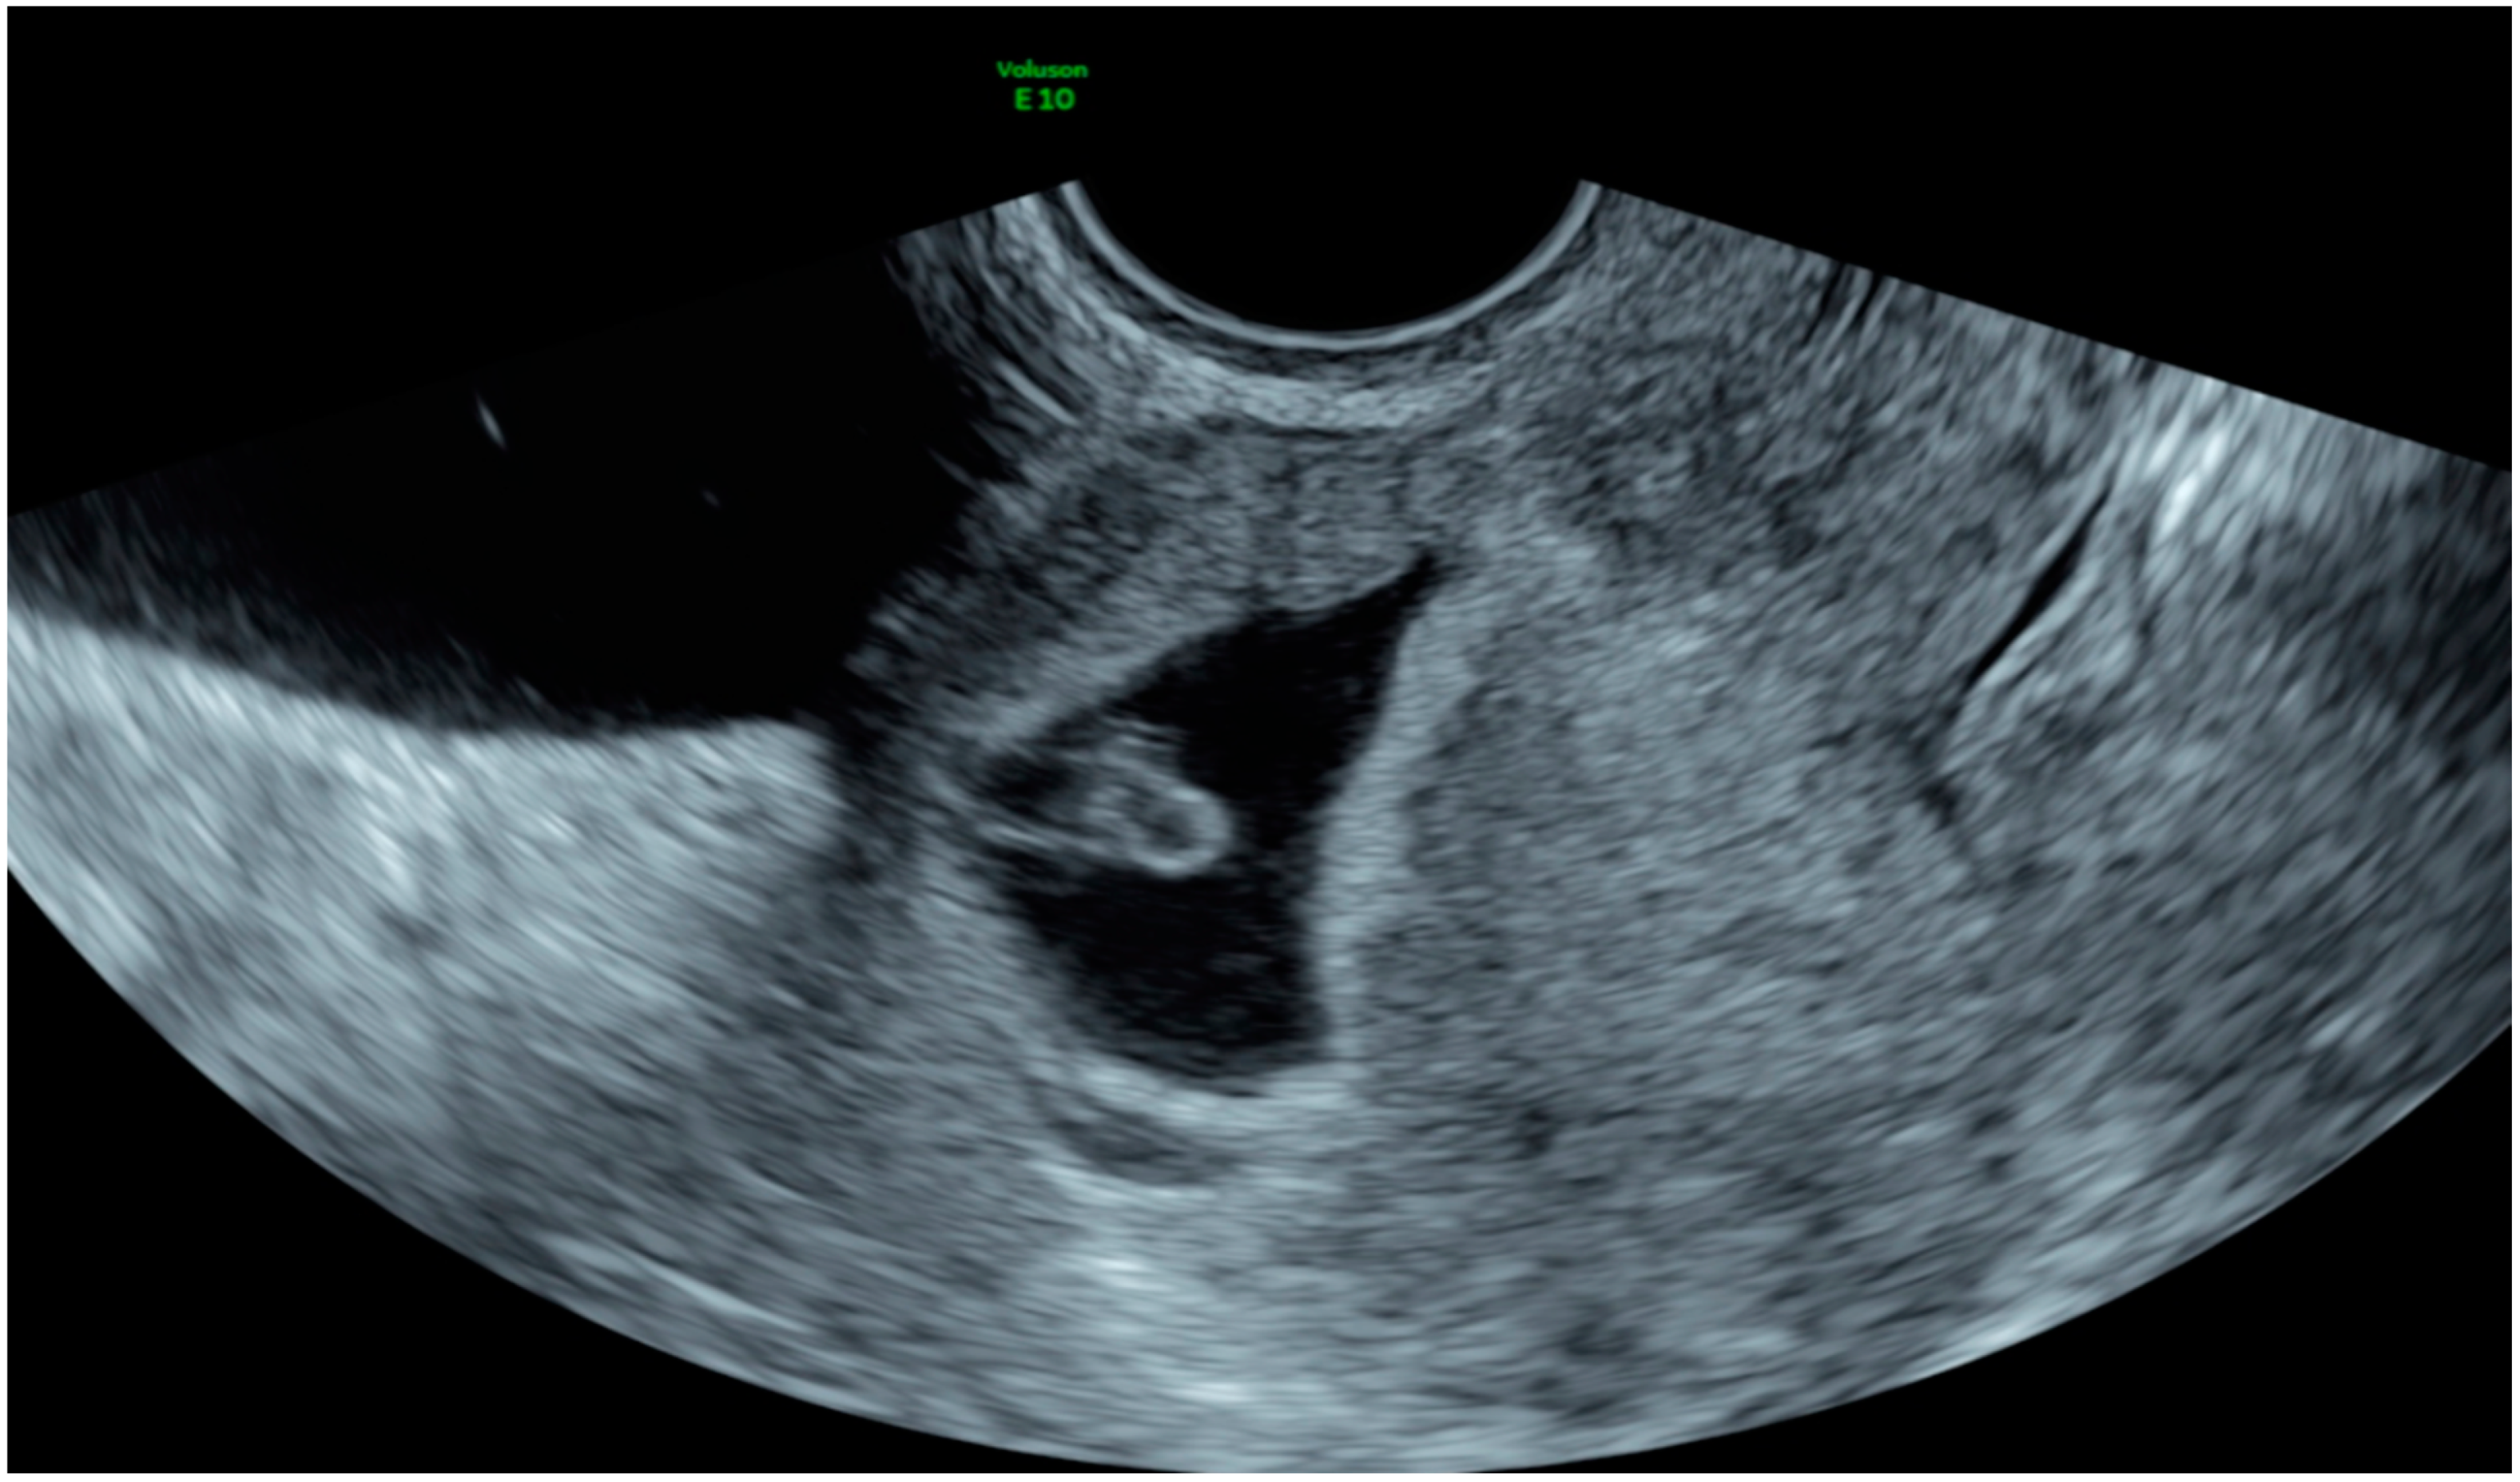

| Case 1 | Brownish vaginal discharge and mild pelvic pain | 7 | 18,048 | GS 15 × 14 mm right horn | MTX IM 50 mg/m2 of body surface | Complete resolution |

| Case 2 | Asymptomatic | 6 | 6579 | GS 6 × 8 mm; right horn | MTX IM 50 mg/m2 of body surface + Mifepristone 600 mcg | Complete resolution |

| Case 3 | Pinkish vaginal discharge | 5 + 3 | 2124 | GS right 12 × 12 horn; N/A | MTX IM 50 mg/m2 of body surface + Mifepristone 600 mg | Complete resolution |